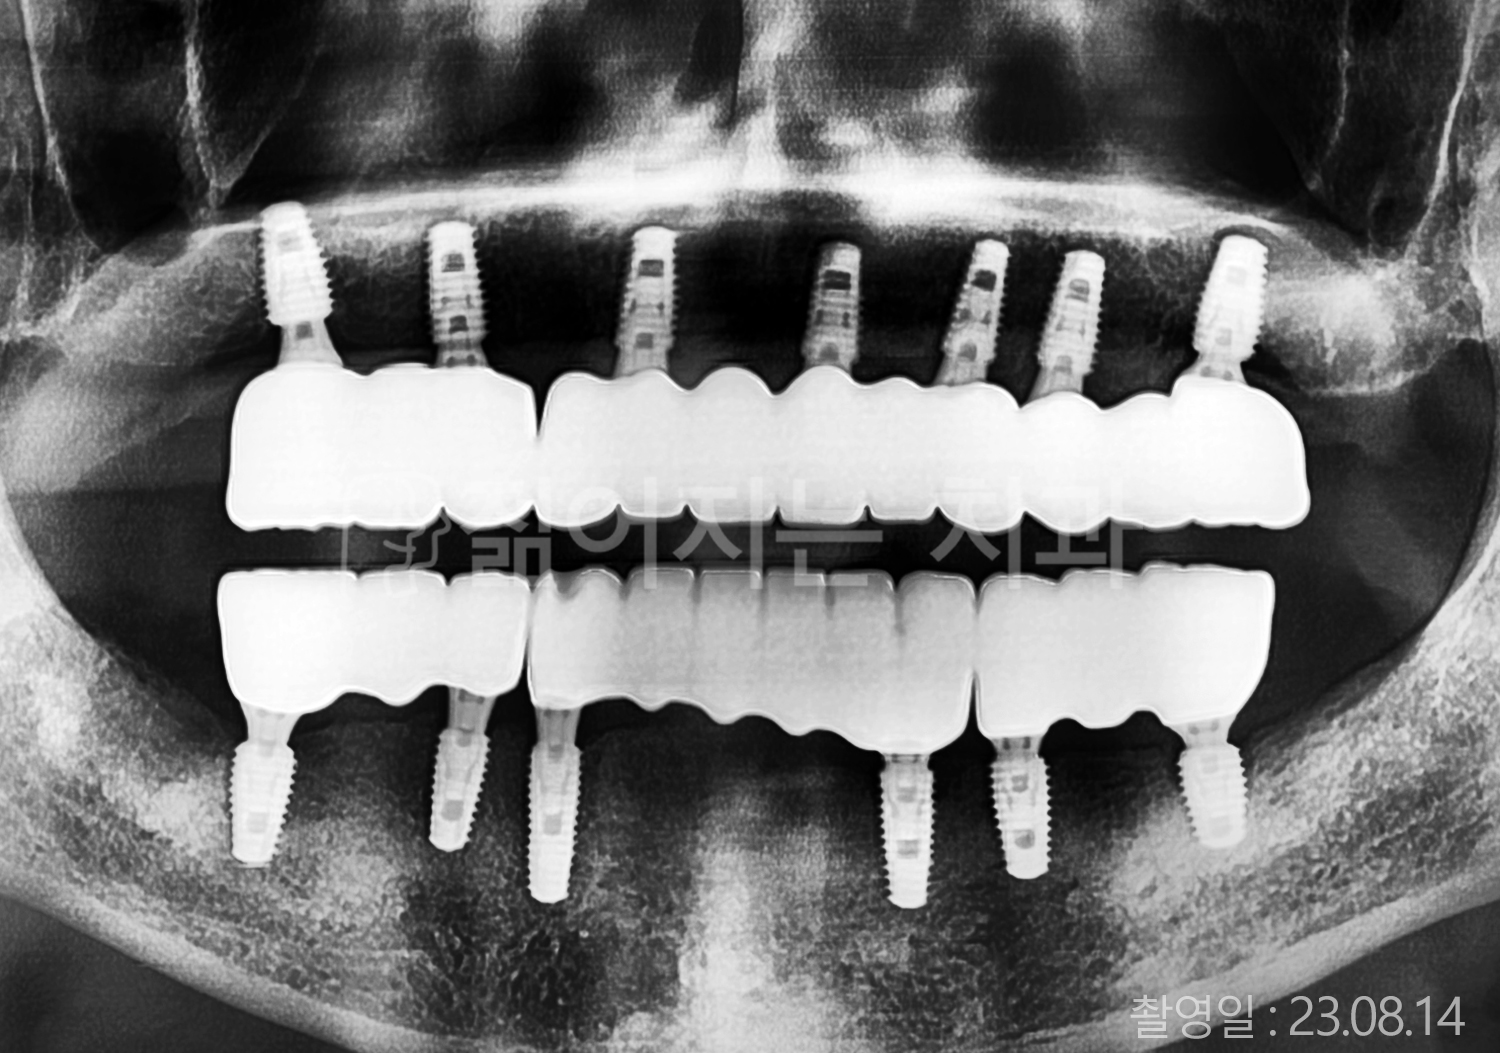

• 60대 전체치아 10개 이상 임플란트

• 50대 전체치아 10개 이상 임플란트